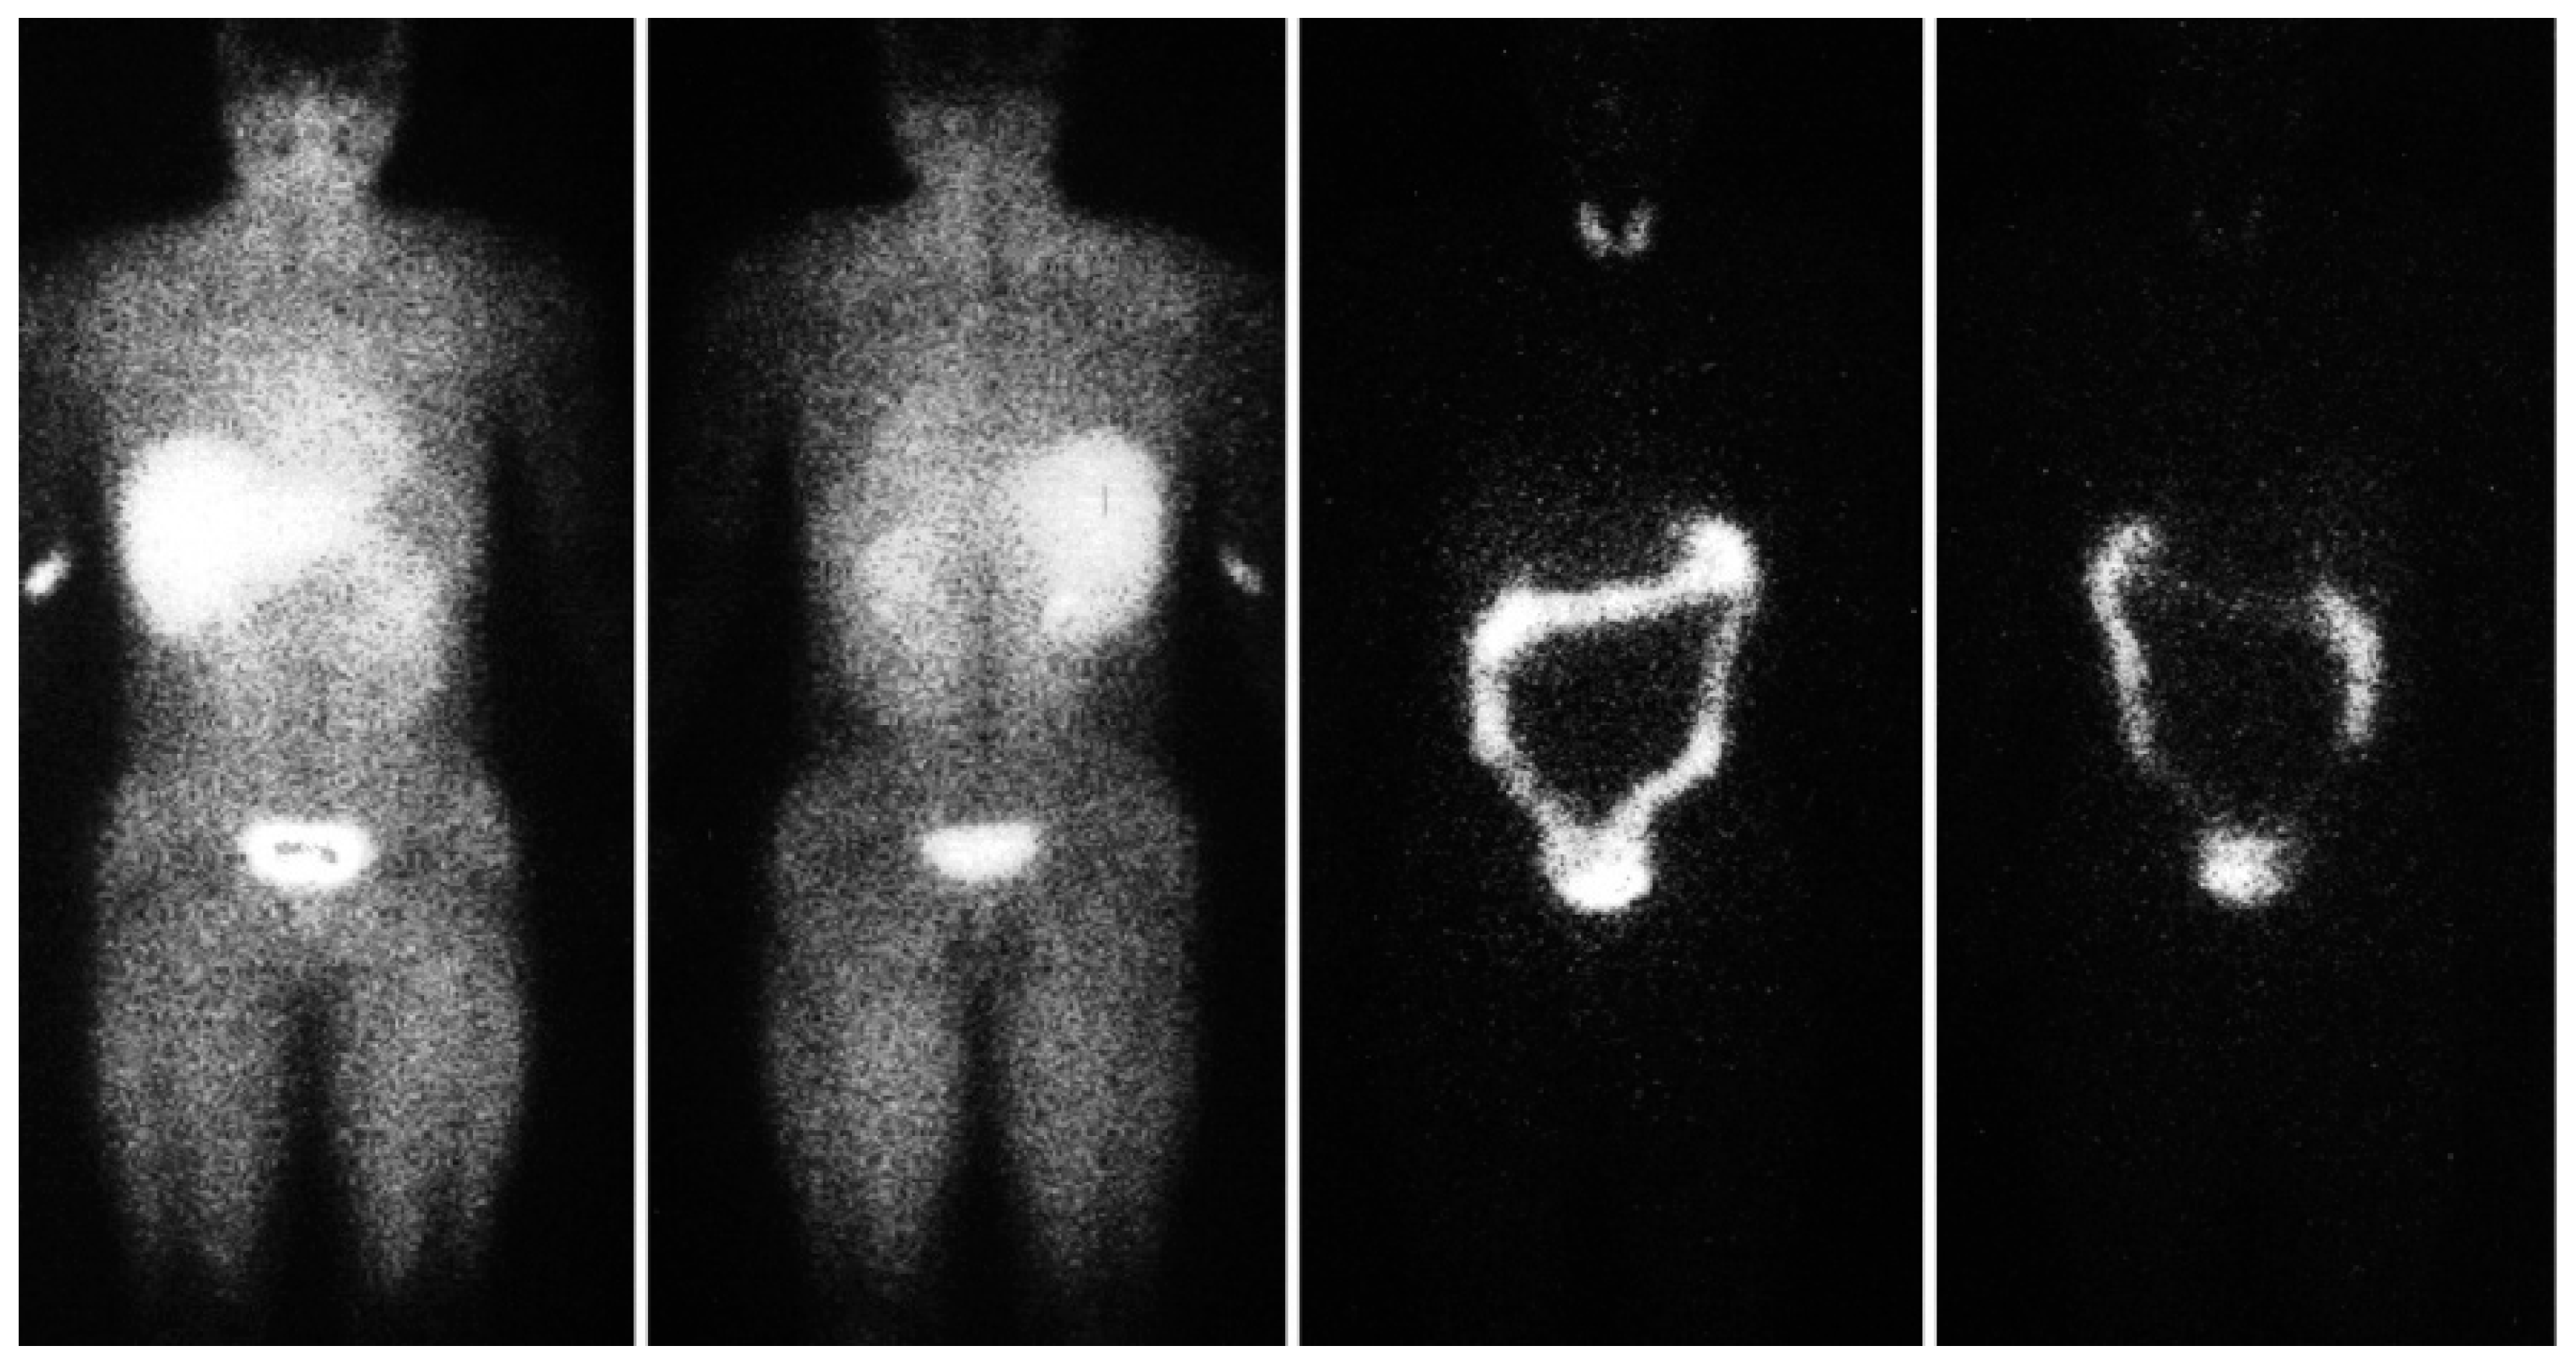

Hypoxia is considered to play a major role in solid cancer growth, metastasis and resistance to treatment; a number of approaches have been developed to address these challenges [6]. The iodine-labelled radiotracer iodoazomycin arabinoside (IAZA) is a first-generation hypoxia imaging agent that binds selectively to hypoxic sites in tumours and other tissues [7]. Image-based pharmacokinetic and radiation dosimetric data for [123I]IAZA have been reported for healthy, exercising, adult volunteers [8] (Figure 1). Data from the diagnostic imaging study of sedentary healthy volunteers supported a classical two-compartment pharmacokinetic model derived from sequential venous blood and urine samples. SPECT region of interest (ROI) image analyses provided comparable total body mean residence times and urinary clearance estimates. ROI data from serial images were used to generate time-activity curves for individual organs to derive detailed radiation dosimetry estimates for 123IAZA [9].

Figure 1. Typical immediate (0–30 min) anterior (left) and posterior (left centre) views and 22 h anterior (right centre) and posterior (right) planar images after 123I-IAZA intravenous administration to volunteers. Images were adapted from Stypinski et al. 2001. [9].